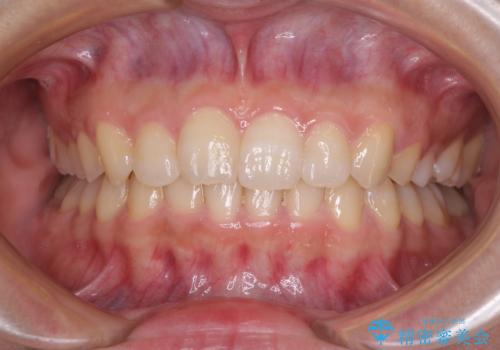

気になる前歯をインビザラインで綺麗に

担当医 藤巻太一朗

ワイヤー矯正歯科治療の注意事項(リスク・副作用など)

- 治療中は違和感や痛みが起こることがあります

- 症状により、抜歯が必要な場合があります

- 治療中は歯磨きがしにくくなるため、虫歯や歯周病になりやすくなります

- 矯正治療後の保定が不十分だと後戻り(元の位置に戻ろうとする動き)をします

- 自費診療(保険適用外)となります